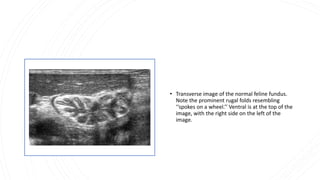

• Transverse image of the normal feline fundus.

Note the prominent rugal folds resembling

‘‘spokes on a wheel.’’ Ventral is at the top of the

image, with the right side on the left of the

image.

• Transverse imageof the normal feline fundus. Note the prominent rugal folds resembling ‘‘spokes on a wheel.’’ Ventral is at the top of the image, with the right side on the left of the image.